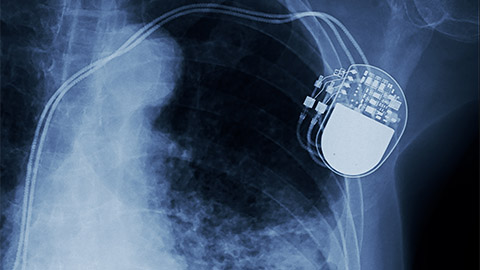

An x-ray image of a pacemaker in the human body.